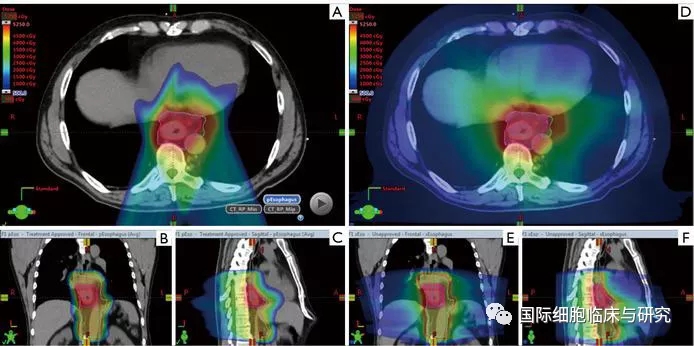

图中所示为质子疗法(左)与光子疗法(右)治疗食道癌的照射范围对比。红色色块区域为照射目标(肿瘤病灶),色块颜色从红色到蓝色示照射剂量逐渐减少。

在两种治疗方案的最高剂量照射区域分布相似的前提下,光子疗法对于周围健康组织造成的照射更严重。即采用质子疗法,能够有效减少患者心脏与肺部受到的照射。

图示为质子疗法(左)和光子疗法(右)的照射范围对比。我们可以清楚地看到,采用质子疗法治疗时,射线在击中病灶部位后剂量迅速降低,对于后方心脏等重要器官造成的放射剂量较小;而光子束在击中病灶部位后,仍然持续穿过患者身体,抵达病灶部位前和抵达病灶部位后的照射剂量几乎一致。